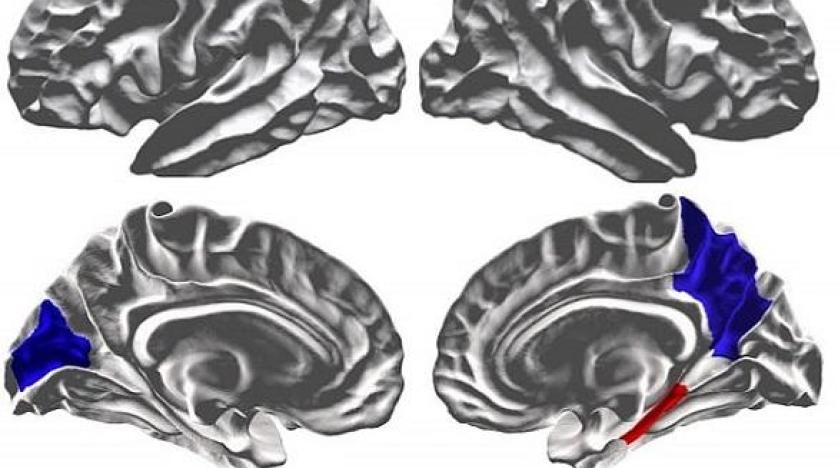

وجاء في بيان الخدمة «أن حجم المادة الرمادية كان أقل بشكل ملحوظ لدى الأطفال المصابين بالتوحد، كما ازدادت لديهم نسبة التعرج في القشرة الدماغية. فيما أظهر التحليل أن المهارات اللغوية تعتمد على سمك المادة الرمادية وشدة التعرج في مناطق القشرة الدماغية التي تشارك في النشاط الكلامي. وتشمل هذه المناطق أقساما من الفص الصدغي والجبهي من القشرة الدماغية».

واكتشف الباحثون أن حجم المادة البيضاء في مناطق مختلفة من الدماغ عند الأطفال كان متشابها، بينما كان حجم المادة الرمادية عند الأطفال المصابين بالتوحد أقل قليلا. وفي الوقت نفسه، وجد الباحثون أن مستوى التعرج بقشرة الأطفال المصابين بالتوحد كان أعلى بشكل عام مما هو معتاد لدى أقرانهم من المجموعة الاختبارية.

وقد أظهرت المقارنة اللاحقة لهذه البيانات مع المهارات اللغوية للأطفال أن المشكلات المتعلقة بنموهم غالبا ما تنشأ عند الأطفال المصابين بالتوحد الذين تميّزوا بسماكة منخفضة نسبيا للمادة الرمادية في الدماغ، فضلا عن أعلى مستوى من التعرق في الدماغ والفص الصدغي والجبهي للقشرة المرتبطة مباشرة بالنشاط الكلامي.